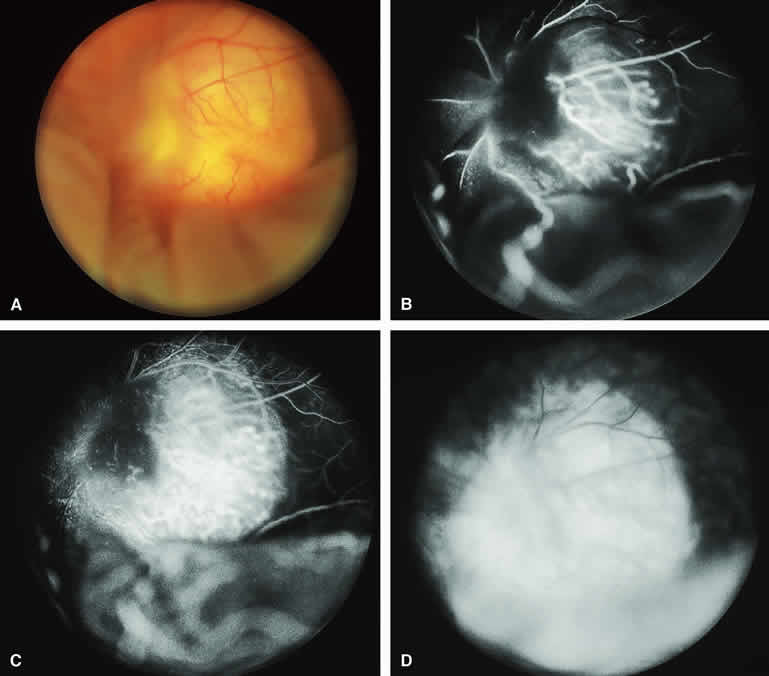

Amelanotic Choroidal Nevus

Approximately 10% to 15% of choroidal nevi are largely or completely amelanotic clinically. Fluorescein and ICG angiography of an amelanotic choroidal nevus (see Fig. 3) tend to show less prominent hypofluorescence of the lesion than they do with darkly melanotic nevi. Because of the lack of intracellular melanin pigment within the nevus cells, some large-caliber choroidal blood vessels running through the nevus may be visible in the region of the mass (see Fig. 3B and C). These choroidal blood vessels are better defined by ICG angiography than by fluorescein angiography. Amelanotic choroidal nevi often appear mildly hyperfluorescent in late-phase frames (see Fig. 3D).